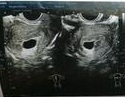

读懂胎儿B超单医生的字向来难懂,做了准妈的更加心急,B超单上那些“专业名词”都代表啥?那些游走...

读懂胎儿B超单医生的字向来难懂,做了准妈的更加心急,B超单上那些“专业名词”都代表啥?那些游走... -

怀孕第18周如果你还没有去B超检查,那么最近要去做一次了。胎儿开始有频繁地胎动了,借助听诊器...

怀孕第18周如果你还没有去B超检查,那么最近要去做一次了。胎儿开始有频繁地胎动了,借助听诊器... -